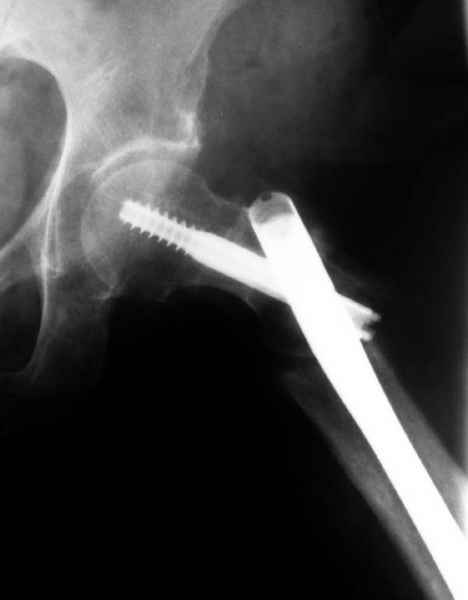

Не стали усложнять интрамедуллярным вариантом коррекции, легче контролировать коррекцию пластиной, поэтому сделали операцию 95 градусной Blade Plate, разогнув до 110 градусов.

Надеемся на успех, потому что до введения пластины дефект от импланта забили костной стружкой и удалось создать компрессию между отломками, максимальную для импланта (150 кило/паунд). Сделана дополнительная костная пластика и за счет измененного угла пластины устранено укорочение конечности.